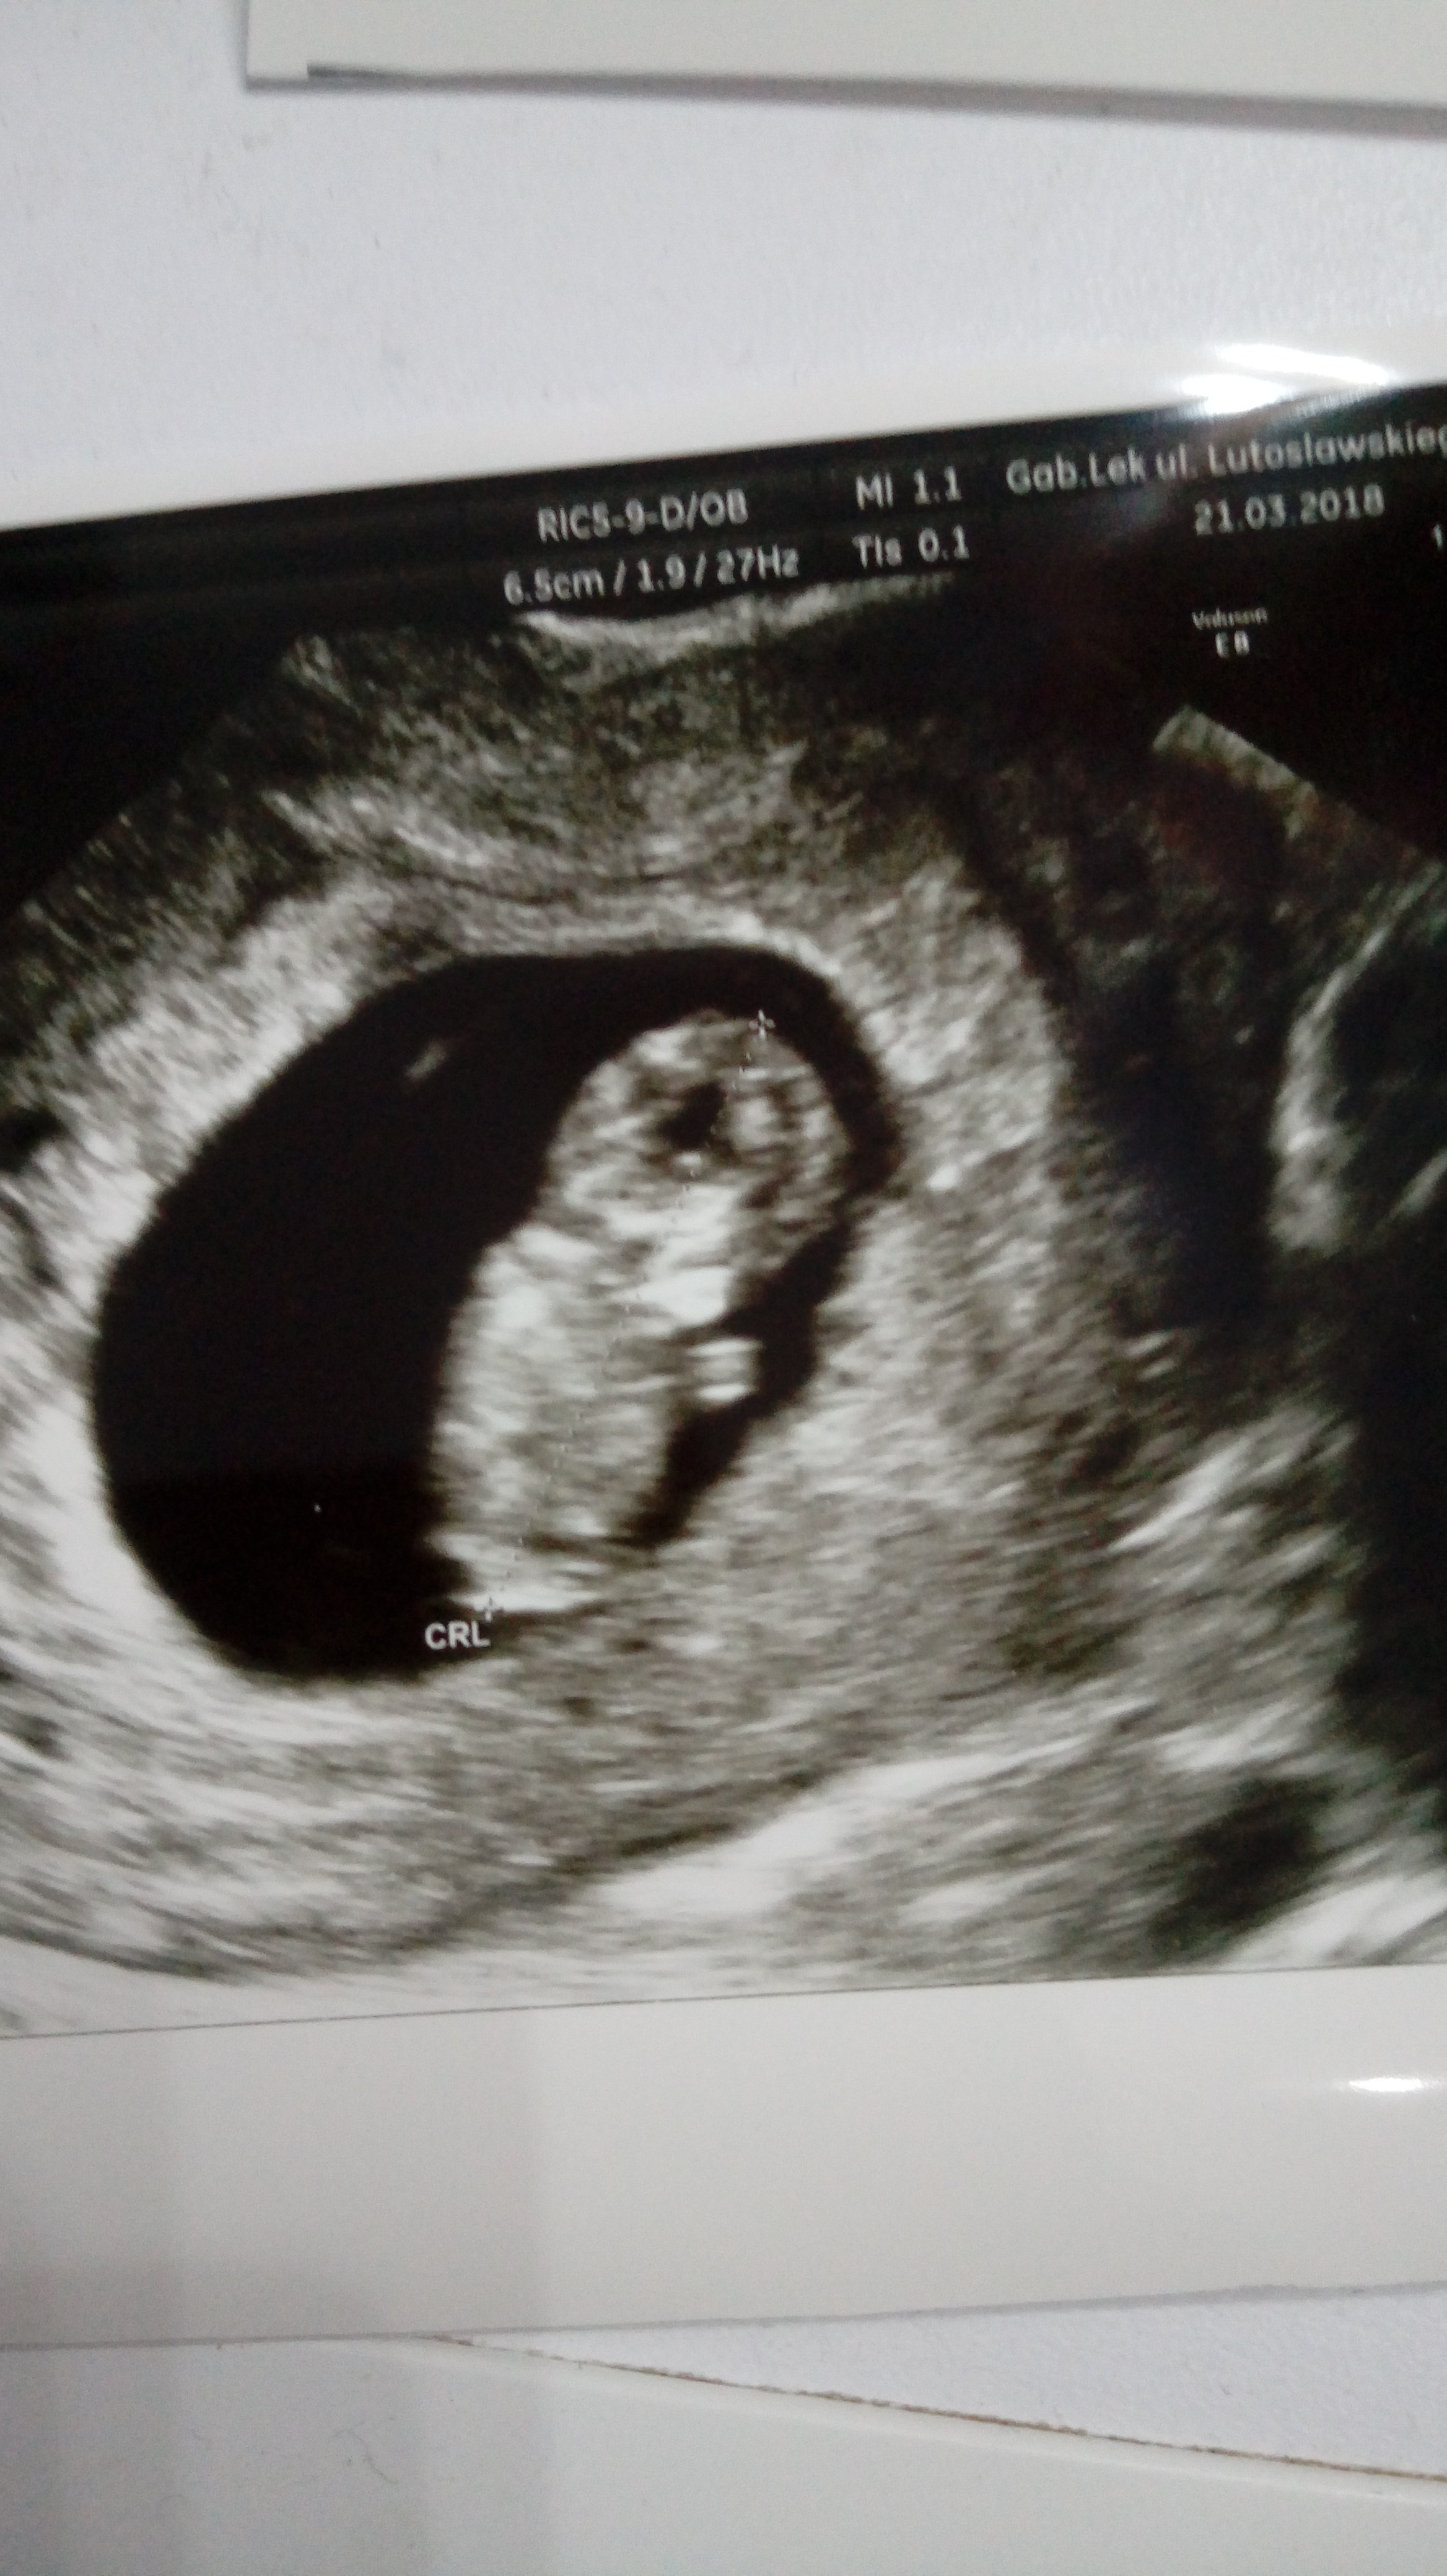

mamy serduszko i 2,60cm z usg wychodzi 9t3d więc narazie tylko jeden dzień różnicy z om. Lekarz pokazał nóżki i rączki i że ma skrzyzowane nóżki i jedną stopką sobie ruszał choć ja tego nie widziałam